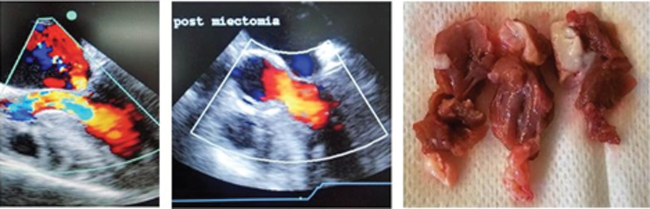

ETE pre y post miectomía (A y B). Miectomía septal ampliada, pieza quirúrgica (C)

El gradiente preoperatorio basal promedio fue de 53,5 mmHg (rango 16-104 mmHg) y provocado de 86,4 mmHg (rango 44-186 mmHg). Vale aclarar que solo un paciente presentó gradiente con maniobras menor a 50 mmHg, pero era portador además de insuficiencia mitral moderada severa secundaria a MAS en esfuerzo y FA paroxística recurrente con descompensación. Los gradientes basal y provocado PO fuero 9,4 mmHg y 13,5 mmHg (p < 0,01). Al seguimiento, los gradientes en reposo y provocados fueron aún más bajos, de 8,3 mmHg y 10,7 mmHg respectivamente. (p: NS) (Figura 2 A y B) (Tabla 3)

Las mediciones del septum variaron entre 16 y 34 mm (media 21,9 ± 4,5 mm) en el preoperatorio. En el PO las mismas fueron de 13,2 ± 3 mm en promedio (p < 0,001). (Figura 2 C).

Los estudios con Doppler color mostraron IM moderada a severa en 32% de los pacientes en el preoperatorio. Se detectó IM moderada asintomática en un paciente al seguimiento (3,5%), sin insuficiencia severa en ninguno de ellos. Tampoco se observó insuficiencia aortica moderada o severa en el seguimiento.